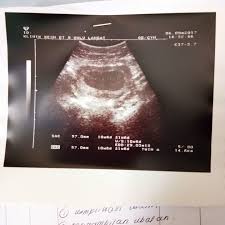

Cuci Rahim Secara Tradisional - Rangkaian Cara Tradisional Mengatasi Kencing Nanah / Dalam proses ini, doktor akan membuka (dilatation) pangkal rahim (servik) dan membuat curettage (mencuci) dalam rahim bagi mengeluarkan janin yang telah keguguran tersebut.

Cuci Rahim Secara Tradisional - Rangkaian Cara Tradisional Mengatasi Kencing Nanah / Dalam proses ini, doktor akan membuka (dilatation) pangkal rahim (servik) dan membuat curettage (mencuci) dalam rahim bagi mengeluarkan janin yang telah keguguran tersebut.. D&c biasanya dilakukan jika janin tidak keluar secara spontan ataupun terdapat banyak pendarahan atau jangkitan berlaku. Cara alami membersihkan rahim tanpa dikuret dengan secara tuntas menggunakan ace maxs obat tradisional pembersih rahim pasca keguguran dan melahirkan. Obat pembersih rahim tradisional obat pembersih rahim tradisional acemaxs untuk membersihkan rahim pasca melahirkan dan tanpa kuret , yang aman dan ampuh untuk membersihkan rahim yang kotor adalah obat herbal ace max's yang dapat membersihkan rahim anda yang kotor secara alami dan tanpa efek samping apapun. Untuk mendapatkan manfaatnya, siapkan 15 gram sambiloto dan 50 gram temu putih. Cara mengobati miom di rahim secara tradisional tanpa operasi.